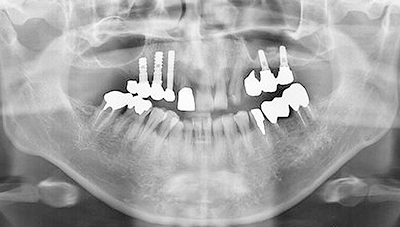

図❶ 初診時のパノラマX線写真

画像所見:パノラマX線写真では、67部の下顎骨体部に淡いすりガラス様のX線不透過像が認められた(図❶)。CT画像では、左側下顎骨体部の骨髄に high density area を認め、また、左側鎖骨胸骨端にも同様の像が認められた。MRI画像で同部の骨髄は、T1W1で低信号、STIRで高信号を呈していた(図❷)。